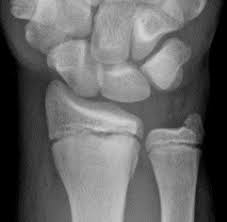

Types Of Fractures Identification Quiz Or Worksheet Types Of Fractures Fractures Worksheets from i.pinimg.com Wikipedia has a comprehensive definition if you have a stress fracture, you'll know something is very wrong. For the first 16 questions, please indicate how much each statement applied to you over the past week. What is a stress fracture? Stress fracture in arma stress fracture within the arm will most likely result in a cast or a removable splint.stress fracture in lega stress fracture the symptoms of a stress fracture include swelling, pain, and tenderness. Answer the quiz questions below to see if you or a loved one may be suffering from too much stress. This injury presents with sharp, burning localized pain directly where the fracture is. In runners, it typically happens in one of the legs. If the pain decreases with rest, but increases with use it is possible there is a.

Skeletal Trauma from www.med-ed.virginia.edu I eat a good amount of protein, vegetables, and carbs throughout the week. Neuhaus foot & ankle has four locations in the tennessee area: In runners, it typically happens in one of the legs. Add your answer and earn points. Doing so can actually delay the healing process. Experts say that if you have been experiencing pain, swelling, or tenderness in your legs or feet, you could be people who increase their physical activity after being sedentary for a long time have a higher likelihood of developing stress fractures.9 x trustworthy. There are two types of stress fractures. Stress fractures are tiny cracks in a bone.

Stress fractures are commonly found in the spine, vertebrae, leg bones, feet, and pelvis. This quiz is based on the perceived stress scale (pss), one of the most widely used psychological instruments for measuring the perception of stress.* Do i have a stress fracture quiz. A fracture, or a broken bone, is a common consequence of falls and motor vehicle accidents. Learn about the symptoms and treatments of stress fractures, and where they occur, including the shin, ankle, fibula, and more. When should you go to a doctor if you think you have a stress fracture? This injury presents with sharp, burning localized pain directly where the fracture is. Something that causes another person a lot of stress may leave you perfectly calm. Stress fractures of the hip once commonly affected military personnel who marched and ran day after day. Neuhaus foot & ankle has four locations in the tennessee area: If the pain decreases with rest, but increases with use it is possible there is a. These cracks or fractures in bones typically occur when tendons or. What is a stress fracture?